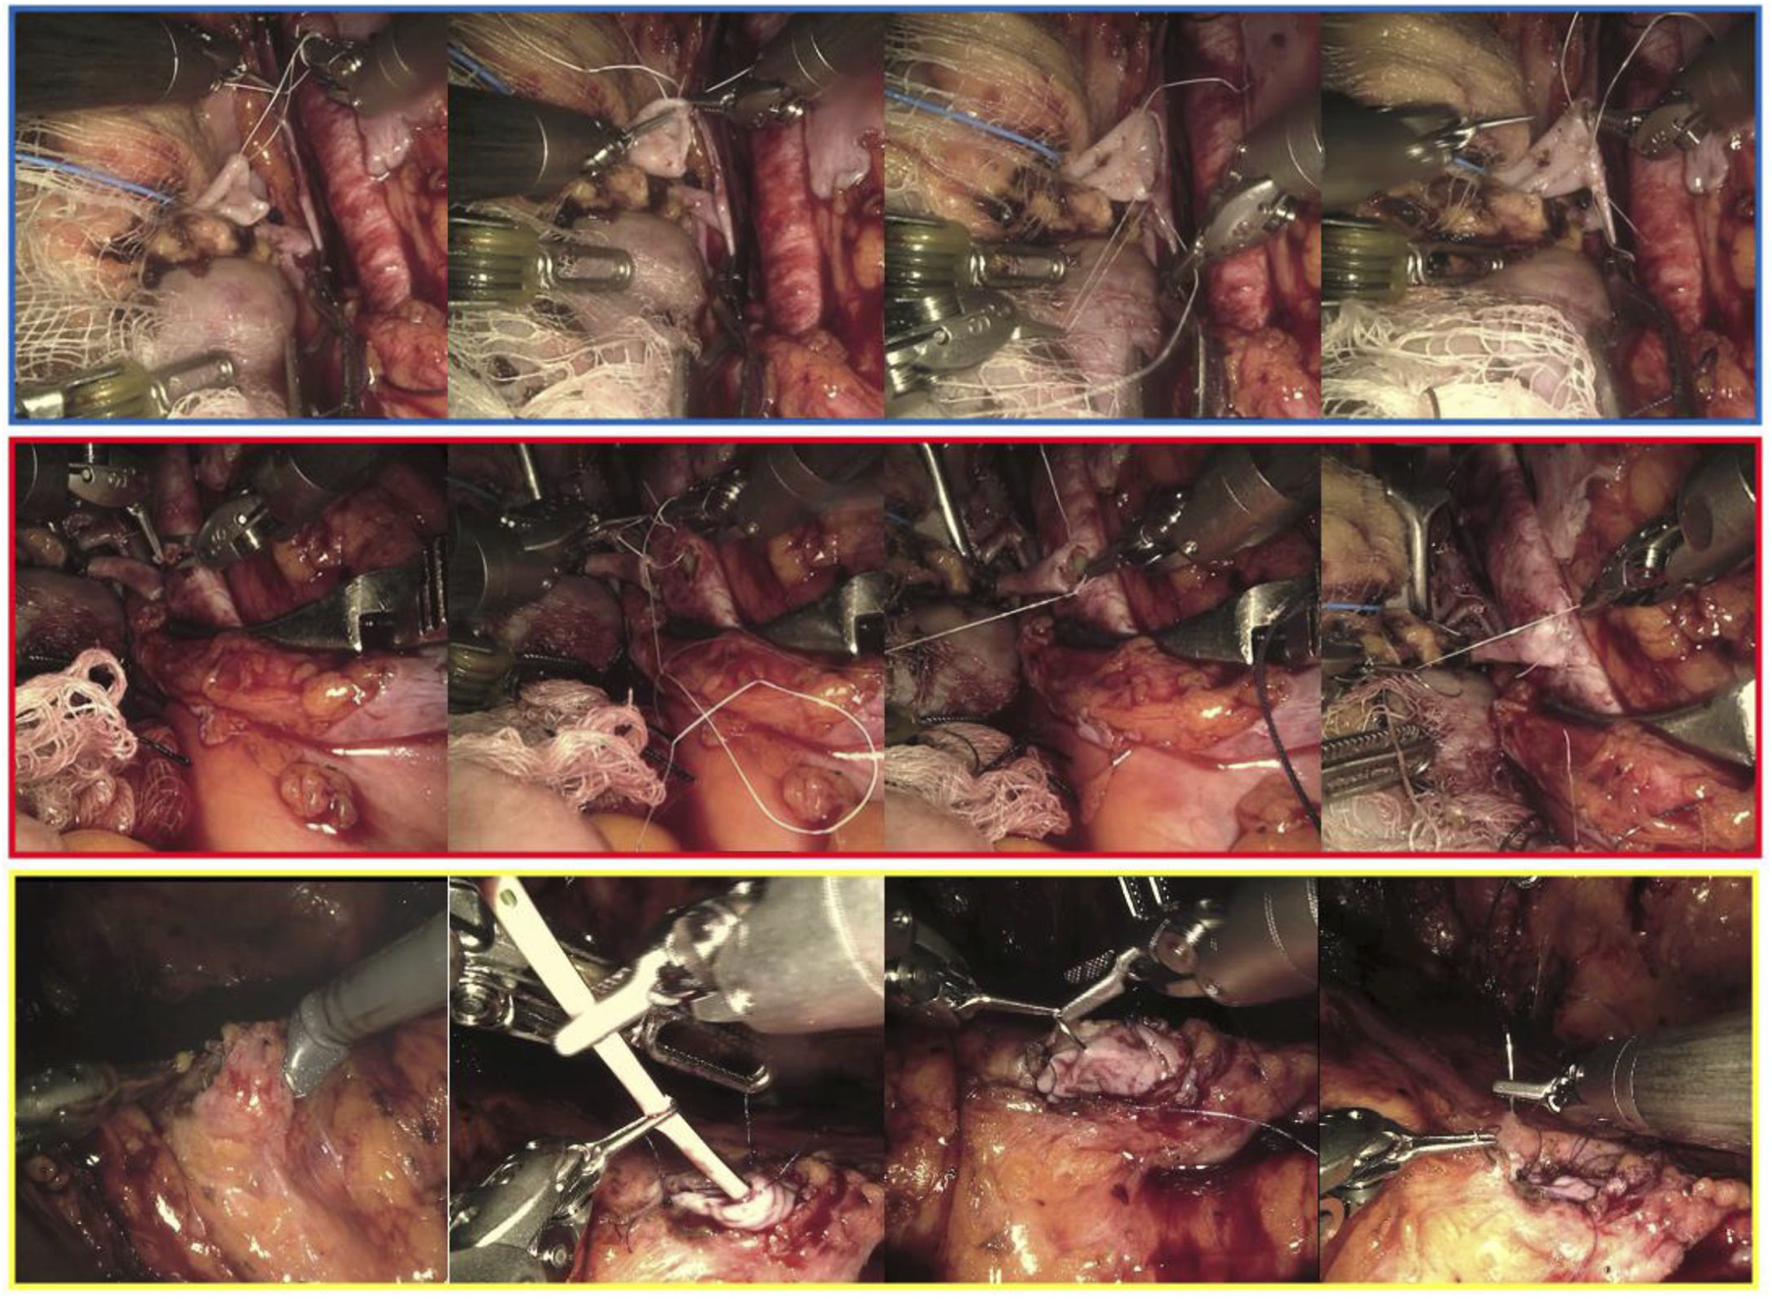

FIGURE 1

Intraoperative snapshots showing the main phases of the venous (framed in blue), arterial (red) and uretero-vesical anastomosis during living donor robotic-assisted kidney transplantation.

RAKTs were performed using the da Vinci Xi Surgical System (Intuitive Surgical Inc., Sunnyvale, CA, USA) in a four-arm configuration, with a 0° lens and a 30° Trendelenburg tilt. The cases were performed by one senior surgeon, who had extensive experience in robotic surgery, robotic-assisted kidney transplantation and open kidney transplantation. In our institution, the RAKT technique followed the principles of the Vattikuti-Medanta technique, using a transperitoneal approach [9, 18]. Briefly, during back-table preparation, the graft is prepared with care to ligate any possible source of bleeding. Then, grafts were wrapped in ice-gauze jackets with marking stitches at the lower pole to maintain orientation before implantation. A small window is created into the gauze for artery and vein exposure. In case of multiples arteries, the surgeon may use different techniques in order to reconstruct the renal artery or decides to perform separate arterial anastomoses during robotic procedure. The graft was then introduced through a Pfannenstiel or periumbilical incision using a GelPoint device. Vascular anastomoses were completed in an end-to-side fashion to the external iliac vessels using a 6-0 GORE-TEX suture (Gore Medical, Flagstaff, AZ, USA) (Figure 1). Graft reperfusion was assessed by intraoperative Doppler-US. Uretero-vesical anastomosis is then completed using extravesical approach, according to modified Lich-Gregoire technique with a doble-J stent (Figure 1). Over time, specific modifications have been made: a) pneumoperitoneum reduction from 12 to 10 mmHg after graft reperfusion in order to reduce possible graft damage [19], b) modification of the graft introduction approach: replacement of the periumbilical incision by the Pfannenstiel incision (allows a quick open conversion if necessary), c) in selected cases, transvaginal approach for graft introduction could be used, d) modification of the organ preservation solution: the historically Ringer’s lactate solution was replaced by histidine-tryptophan-ketoglutarate solution after first cases of RAKT in order to minimize cell damage.